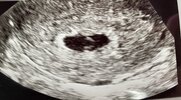

Dziewczyny przedstawiam mojego Smoka 🥰😍 tydzień ciąży 7+0, karta ciąży założona , serduszko pięknie bije. Jestem taka szczęśliwa 🤩